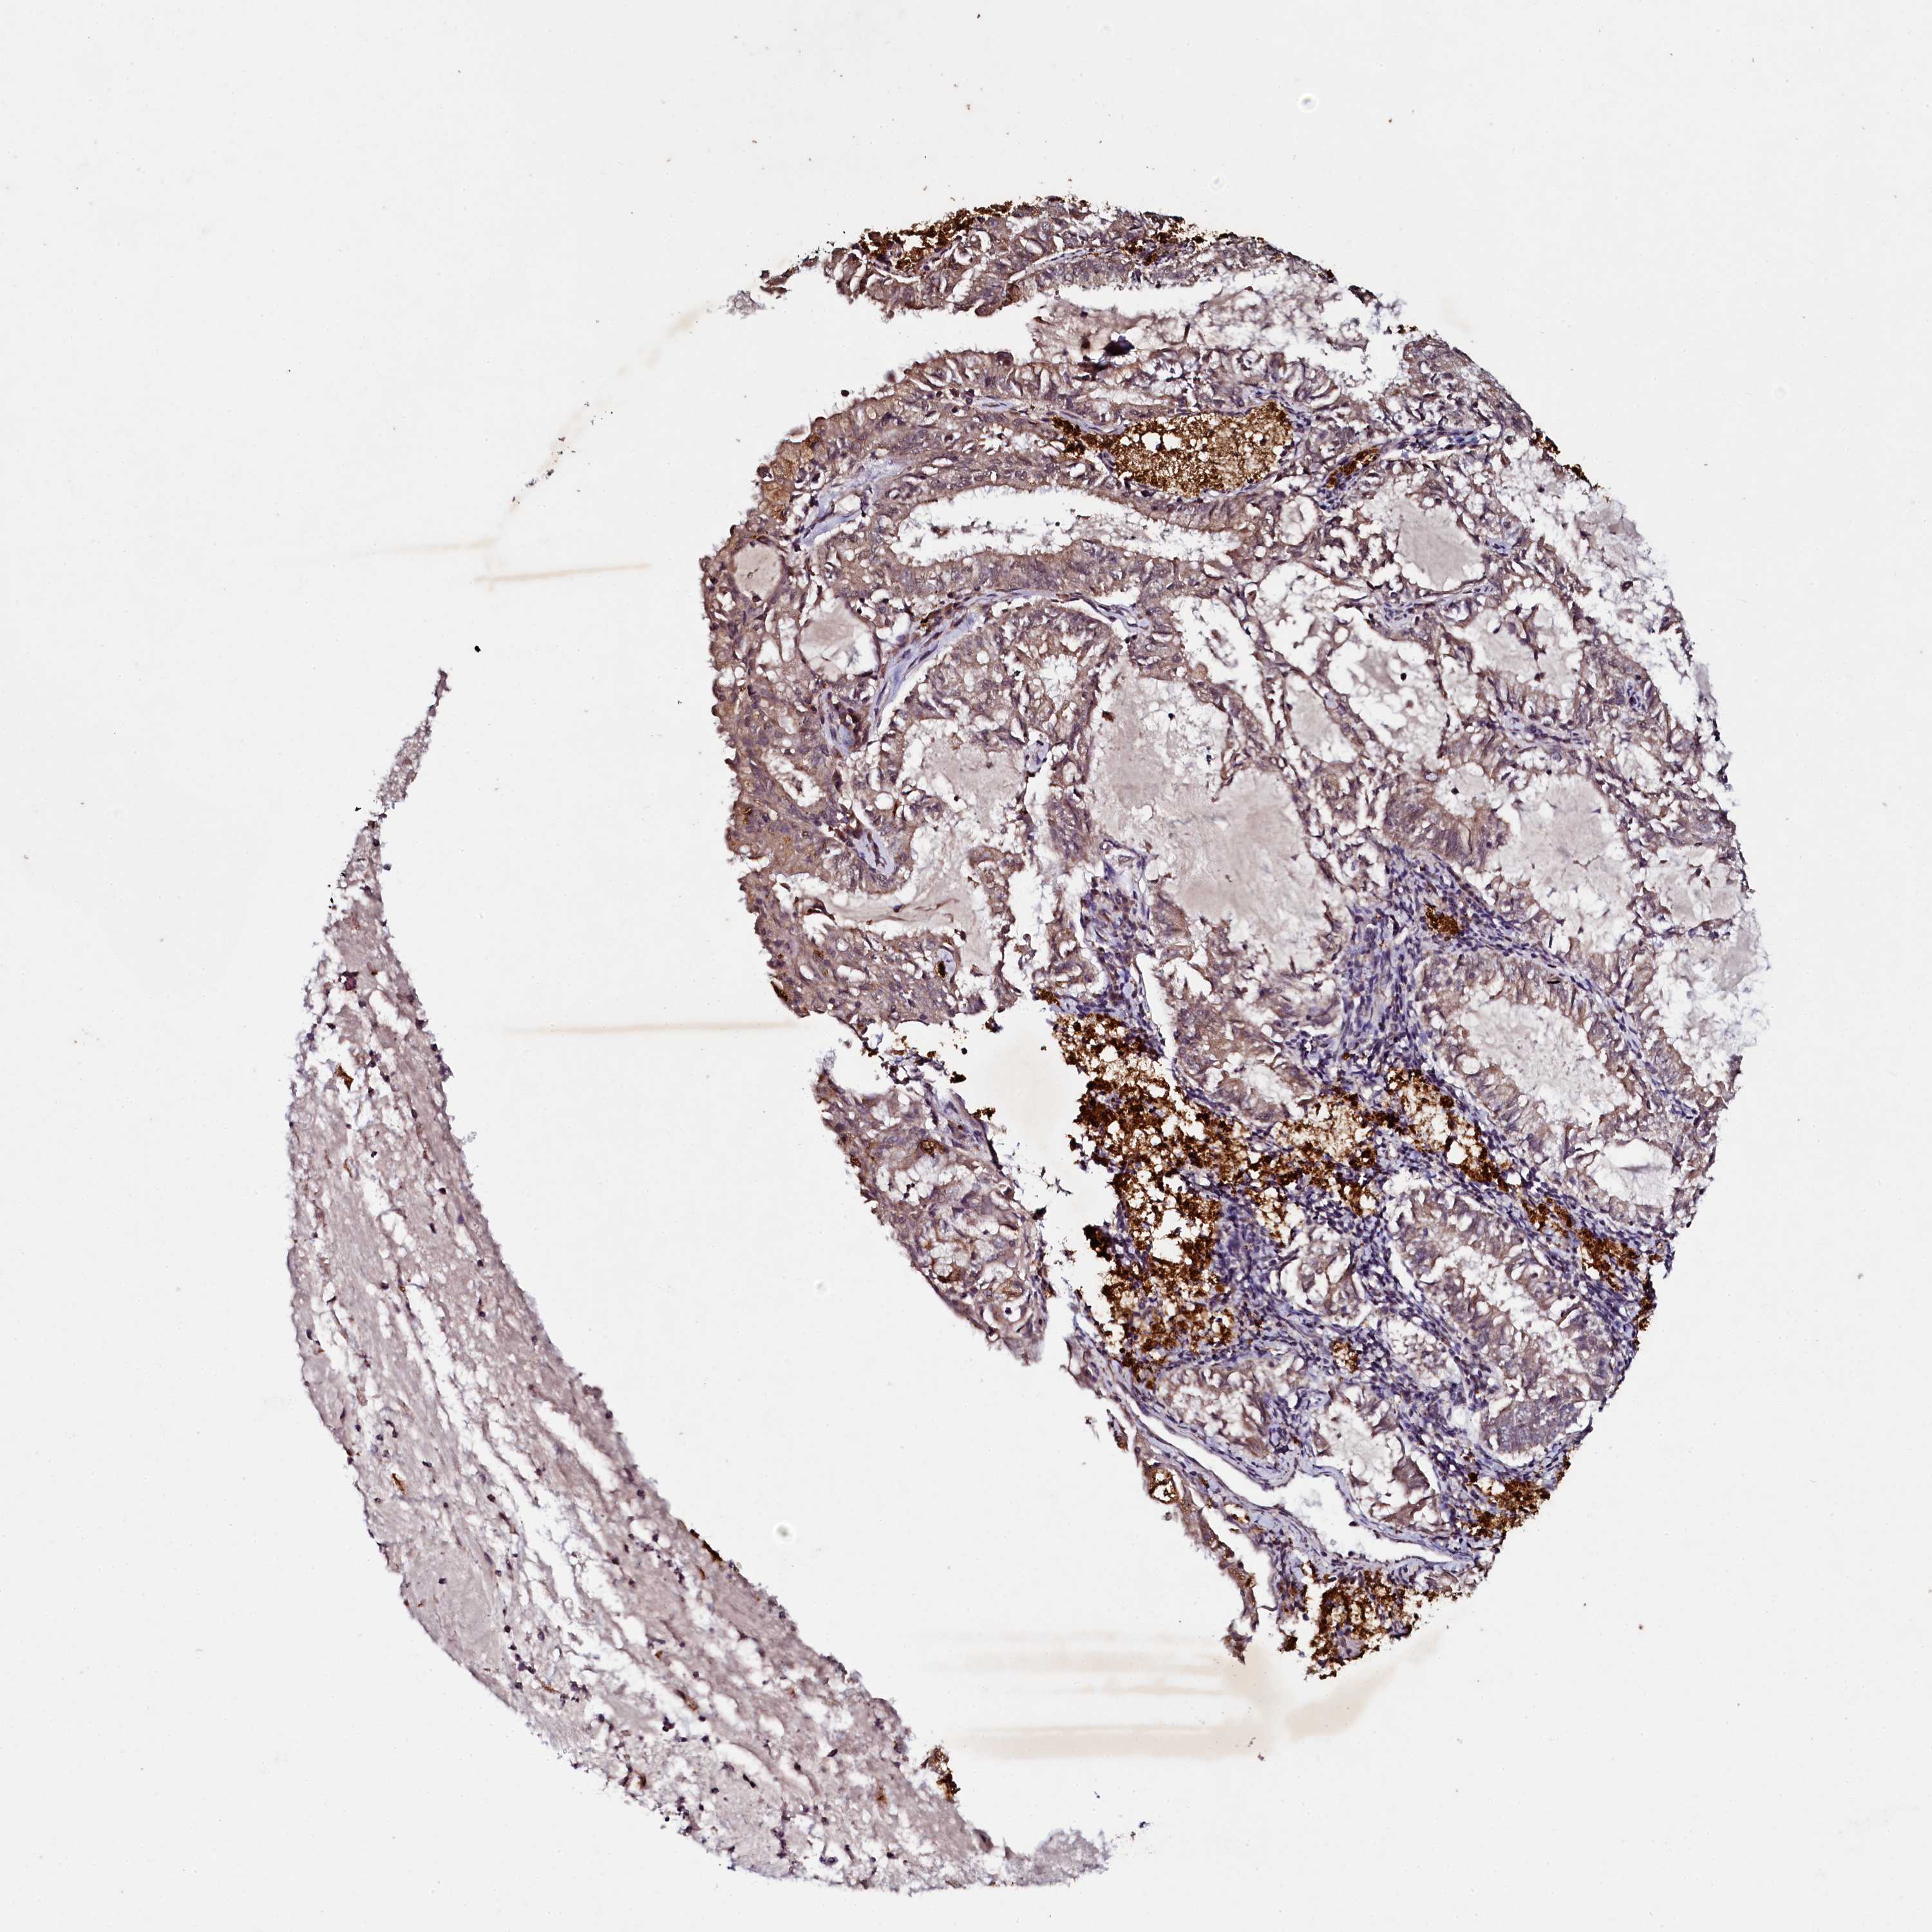

ENDOMETRIAL CANCER - Protein expressioni

A mouse-over function shows sample information and annotation data. Click on an image to view it in a full screen mode. Samples can be filtered based on level of antibody staining by selecting one or several of the following categories: high, medium, low and not detected. The assay and annotation is described here.

Note that samples used for immunohistochemistry by the Human Protein Atlas do not correspond to samples in the TCGA dataset.

Antibody stainingi

Antibody staining in the annotated cell types in the current human tissue is reported as not detected, low, medium, or high, based on conventional immunohistochemistry profiling in selected tissues. This score is based on the combination of the staining intensity and fraction of stained cells.

Each image is clickable and will lead to virtual microscopy that enables deeper exploration of all samples and also displays staining intensity scores, fraction scores and subcellular localization as well as patient and tissue information for each sample.

Antibody HPA040196

Antibody HPA040213

Staining

High

Medium

Low

Not detected

Intensity

Strong

Moderate

Weak

Negative

Quantity

>75%

75%-25%

<25%

None

Location

Nuclear

Cytoplasmic/membranous

Cytoplasmic/membranous,nuclear

Adenocarcinoma, NOS

Adenocarcinoma, metastatic, NOS